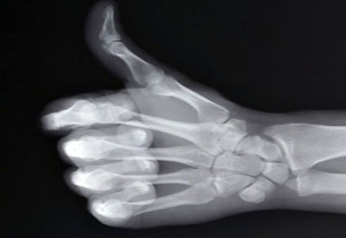

뼈는 우리 몸의 기초이며, 균형과 안정을 유지하고, 다양한 영양소를 저장하는 우리 몸의 필수적인 부분입니다. 뼈 건강을 관리하는 것은 전반적인 건강에 긍정적인 영향을 미치므로 뼈 건강에 좋은 음식을 자주 먹고 뼈 건강에 좋은 습관을 갖는 것이 좋습니다. 그럼 이번에는 뼈 건강에 좋은 음식과 습관에 대해서 한번 알아보겠습니다.

상기와 같이 뼈가 가장 중요합니다. 우리 신체를 지탱해 주는 뼈 건강 항상 관리하시고 챙기셔서 건강한 생활 하세요.